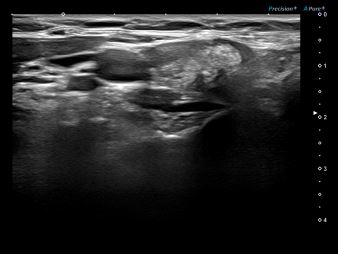

상기환자 우측 목에 만져지는 멍울 있어 내원하신 40대 여성분으로

의심스러운 갑상선 우엽 세침검사 결과 갑상선암으로 진단되었습니다.